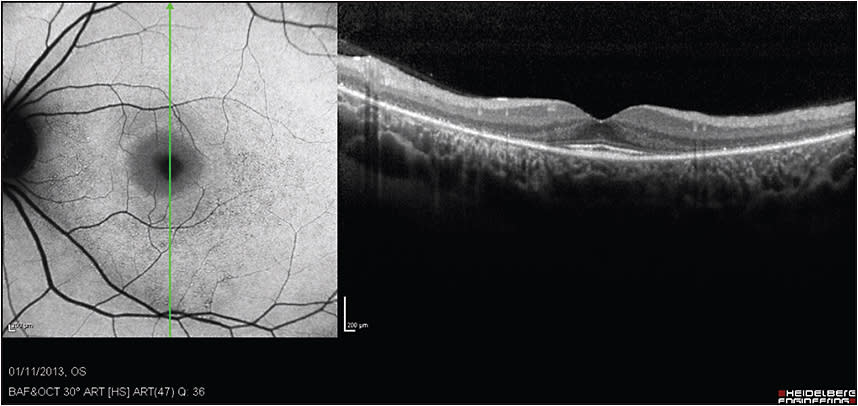

Figure 1. SD-OCT imaging of a 29-year-old woman treated with a daily dose of 400 mg of HCQ for 14 years. She complained of some disturbance in night vision. Her visual acuity was 20/20.

COURTESY OF HADAS NEWMAN, MD

Figure 2. SD-OCT imaging demonstrates perifoveal thinning of the ellipsoid layer and outer retina, with a preserved central fovea (the “flying saucer” configuration). FAF imaging demonstrates perifoveal hyperautofluorescence, surrounded by granular hyper-/hypoautofluorescence.